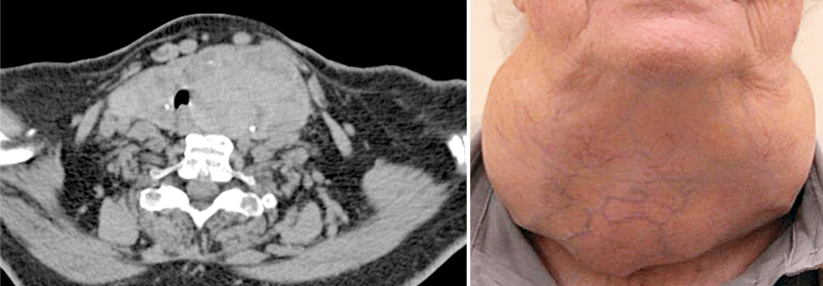

Das differenzierte Schilddrüsenkarzinom (DTC) tritt seit Mitte der 1970er-Jahre immer häufiger auf: In den USA hat sich die Inzidenz bis Mitte der 2010er-Jahre etwa verdreifacht, und parallel nahm die Anwendung der Radiojodtherapie zu. Epidemiolog:innen um Dr. Dr. Elisa Pasqual vom National Cancer Institute, Rockville, wollten wissen, ob dadurch – vor allem bei jüngeren Betroffenen – neben dem bekannten erhöhten Leukämie-Risiko auch die Gefahr für solide Sekundärtumoren steigt.

Das Risiko für die Entwicklung solider Tumoren war gegenüber der nicht mit Radiojod behandelten Kontrollkohorte signifikant um 23 % erhöht (Risk Ratio [RR] 1,23; 95%-KI 1,11–1,37). Aufgeschlüsselt auf einzelne Lokalisationen fiel dies für das Uteruskarzinom signifikant aus (RR 1,55; 95%-KI 1,03–2,32); nicht-signifikante Erhöhungen fanden sich für Speicheldrüsen- (RR 2,15), Magen- (RR 1,61), Lungen- (RR 1,42) und weiblichen Brustkrebs (RR 1,18). Am höchsten war das Risiko bei den Personen, die mind. 20 Jahre überlebt hatten. Dies galt für alle soliden Tumoren (RR 1,47) und für die häufigste maligne Krebsart, das weibliche Mammakarzinom (RR 1,46).

Betrachteten die Forschenden die rund 32.000 Teilnehmer:innen, die ihr DTC mindestens zwei Jahre lang überlebt hatten, so war in der Radiojodtherapie-Kohorte das Risiko für hämatologische Tumoren (RR 1,51; 95%-KI 1,08–2,01) und insbesondere für Leukämien erhöht (RR 1,92; 95-KI 1,04–3,56). Die Autor:innen errechneten, dass geschätzte 6 % der soliden und 14 % der hämatologischen Malignome bei jungen Überlebenden eines DTC auf die Radiojodtherapie zurückgeführt werden könnten. Das sei aber eine konservative Annahme, weil das Studiendesign nicht auf die Schätzung von Risiken über die gesamte Lebenszeit angelegt war.